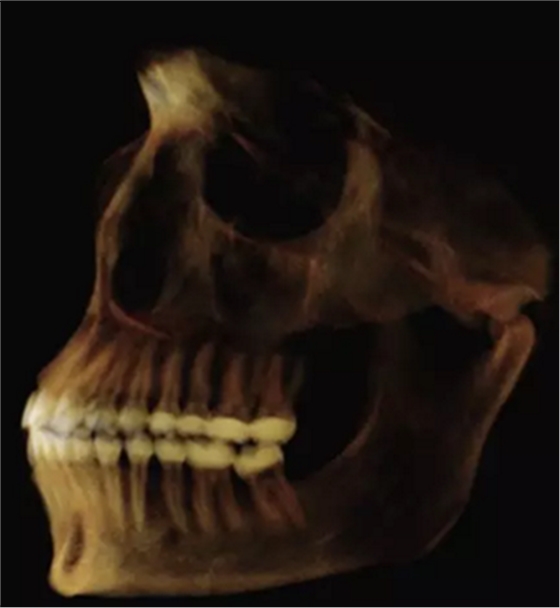

使用體內(nèi)軟件,第一次融合包括咬合導板在下頜牙齒上定位(圖7)。 圖8顯示了咬合導板和下頜骨(類似咬合導板/游離下頜骨)的完整定位。第二次融合涉及咬合導板的上頜牙齒與顱骨上的的上頜牙齒的定位(圖9)。除了原始的下頜骨最小牙尖分離的3D模型(圖10)之外,這將產(chǎn)生一個構(gòu)建好的下頜骨完全咬合的3D模型。

圖10.在顱骨,導板和下頜骨定位之后,最大牙尖交錯位的最終模型。